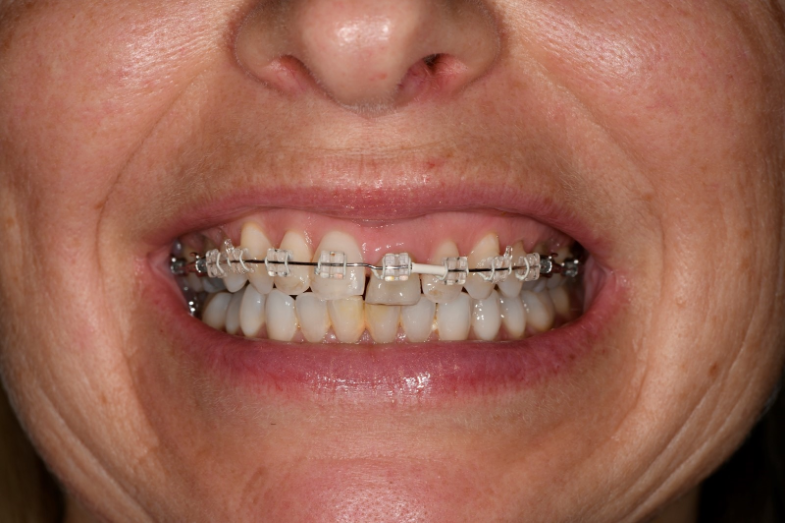

What happens if you have a case like the one below where you have preps and implants?

This is an example of a bigger case – one where we wanted to be able to incorporate the fixture position of the implants into the model.

To solve this puzzle, we had to use Kiwi ingenuity.

As a result, the benefits we were seeing in our conventional workflows could also be applied to our implant cases.

You can see in the series of images below, courtesy of Ashley Bryne, how we did this.